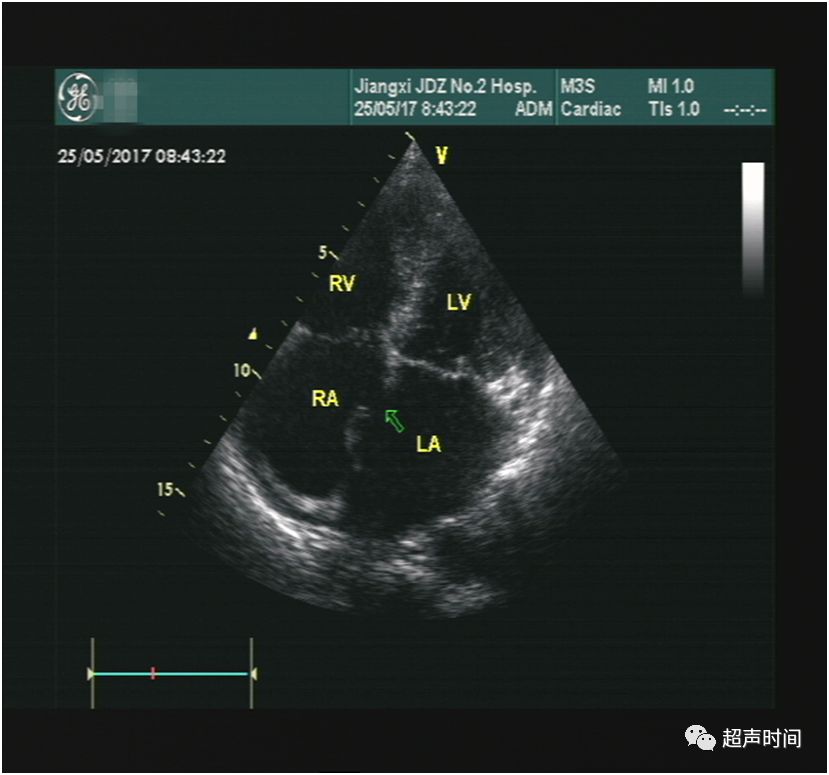

超声所见:M 型超声显示二尖瓣呈平台样改变,前后叶同向运动,回声增厚增强,开放受限,开放幅度约 0.94 cm,描迹瓣口面积约 1.8 cm²(图 1 和 2)。频谱多普勒示二尖瓣前向血流增快,PHT 估测瓣口面积约 1.8 cm²(图 3)。CDFI 示收缩期三尖瓣可见轻中度反流,据此估测的肺动脉收缩压正常(图 4)。房间隔中部见约 1.2 cm 连续中断,可见连续性左向右分流血流信号,峰速115 cm/s (图 5~图 7)。

图 1 M 型超声示二尖瓣的平台样改变

图 5 心尖四腔切面显示房间隔中部的缺损